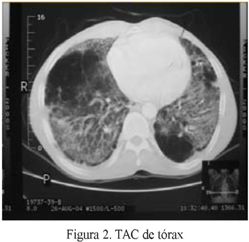

Tomografía de Tórax: infiltrados alveolares bilaterales con áreas en vidrio esmerilado, con zonas hiperlucidas compatibles con bulas (figura 2)

La radiografía de tórax presenta lesiones intersticiales y en ocasiones alveolares, centrales, bilaterales con áreas hiperlucidas en las bases. La tomografía de alta resolución presenta nódulos, opacidades en vidrio esmerilado, patrón en árbol de gemación, lesiones acinares, bandas parenquimatosas, engrasamiento intersticial peribroncovascular, cavernas, patrón reticular, bulas y bronquiectasias por tracción. Esta forma clásica se presentó en nuestro caso, pero posiblemente asociado a enfermedad pulmonar obstructiva crónica EPOC. La resolución dejó fibrosis pulmonar (5).